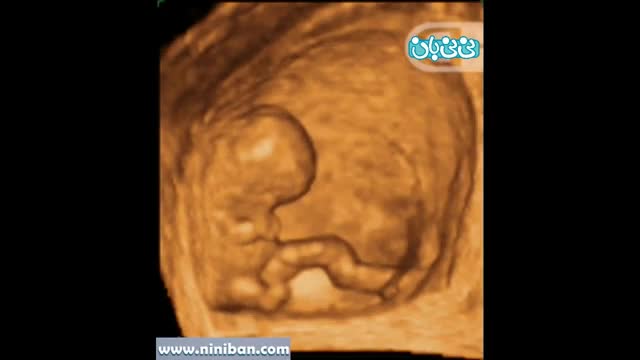

سونوگرافی چهار بعدی هفته هفتم بارداری

۰۰:۲۶